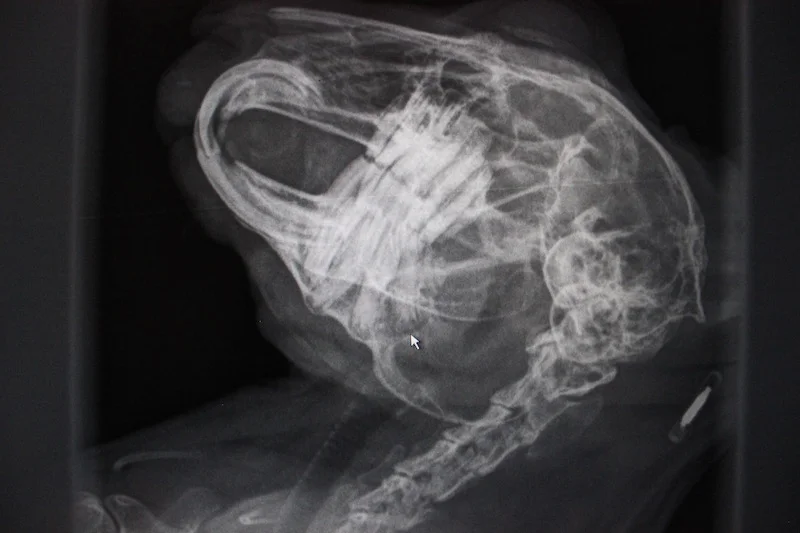

En rask titt på tennene til Teddy viste at vi burde ta røntgen for å få en helhetlig sjekk. Det er helt nødvendig med røntgen for å få en god forståelse av hva som foregår i kaninens munn, så vi gikk inn på røntgenommet.

Dessverre viste røntgenbildene at det ikke var noe håp for Teddy. Han hadde allerede smerter forbundet med tannrøtter som vokste ut av kontroll og annen feilstilling av tannsettet. Dette ville ikke være mulig å gjøre noe med. Dette viser også hvor viktig det er å ta røntgen når man mistenker at noe er galt, og at endringer kan skje hurtig. For fire måneder siden så røntgenbildene av Teddy helt annerledes ut, og kaninkyndige veteinærer trodde og håpte da at et godt og høybasert kosthold ville reversere de tannproblemene han hadde. Han hadde også gått opp flere hundre gram og på mange måter vist fremgang. Allikevel gikk det ikke bra.

Teddy ble ikke med hjem fra klinikken den dagen. Det eneste riktige var å la ham slippe mer ubehag når vi så tydelig hadde sett hvor ille det stod til i munnen hans. Han fikk aldri et eget hjem, men levde godt og var glad og aktiv de månedene han var i fosterhjem. Dessverre var det ikke noe å gjøre med de problemene han hadde, og vi ser at pelsmidden kun var et overfladisk symptom på et større problem.

Teddy viser hvorfor røntgen er helt avgjørende for å få en forståelse for hvordan tilstanden i munnen er. Foto: Marit Emilie Buseth